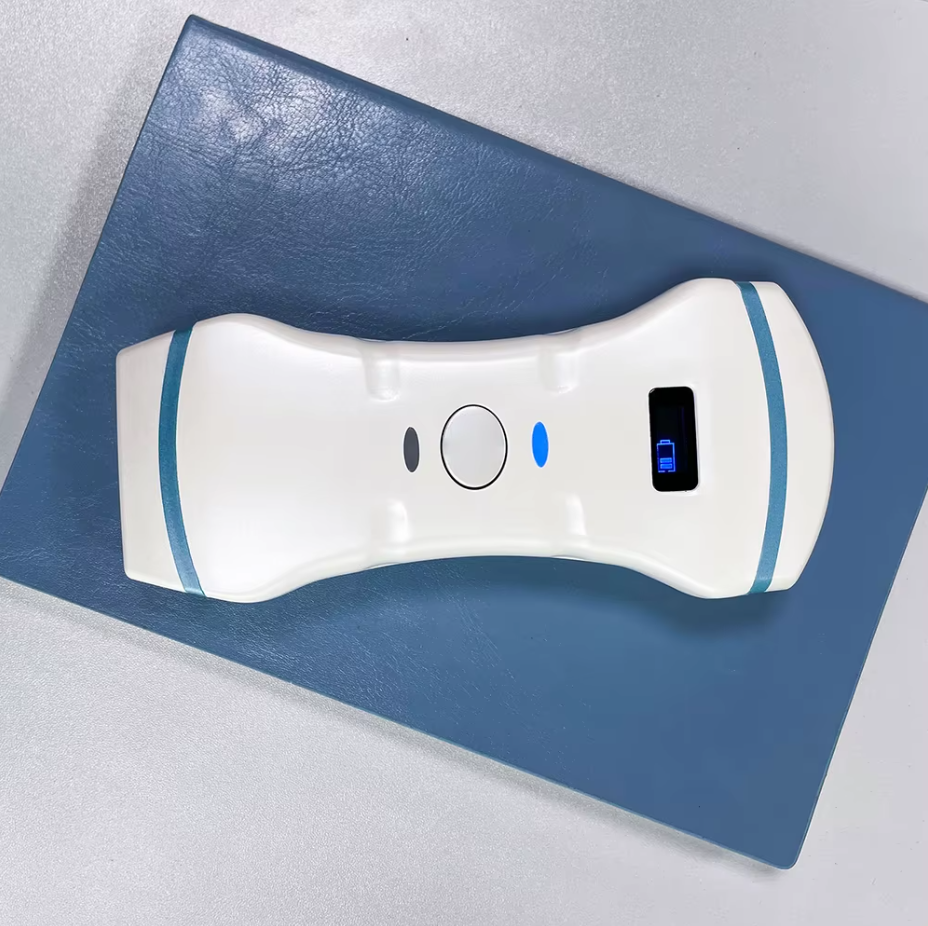

El B.S.D. CU45 es un ecógrafo digital Doppler color portátil profesional que combina potentes modos de imagen (B, dual-B, quad-B, M-mode, Doppler color, PW, CW, PDI y THI). Incluye un monitor LED de 12,1”, disco duro de 500 GB para almacenamiento, clasificación médica CE, construcción robusta y portabilidad avanzada, ideal para aplicaciones clínicas compartidas en humanos y animales.

TRANSDUCTORES INCLUIDOS: Lineal, Convexo

Portabilidad profesional: su diseño robusto y compacto lo convierte en una herramienta ideal tanto para hospitales como para clínicas móviles o veterinarias de campo.